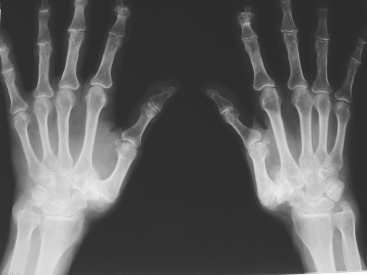

Die Röntgenaufnahme der betroffenen Hand zeigt im Bereich des Daumensattelgelenkes einen verschmälerten bis aufgehobenen Gelenkspalt. Die gelenknahen Knochenanteile sind verändert (Sklerose, Zysten). Weiterhin zeigt das Röntgenbild Knochenzacken im Bereich des Daumensattelgelenkes, die teilweise weit in die umgebenden Weichteile hineinragen.